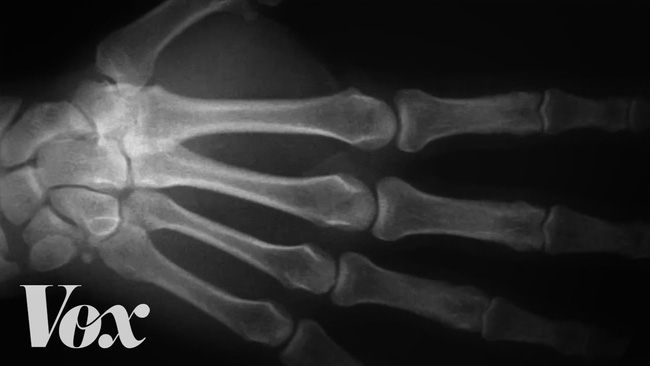

Có những thói quen xấu mà nhiều người mắc phải, trong đó có bẻ ngón tay. Bẻ ngón tay sẽ khiến khớp tay trở nên to, liệu có đúng như vậy không? Hành động tưởng chừng như giúp bạn có cảm giác thoải mái này là một quá trình diễn ra trong cơ thể đã được khoa học phân tích.

Khi bị mỏi, không ít người có thói quen là bẻ khớp ngón tay của mình. Hành động này khiến bạn có cảm giác thoải mái, nhưng có người cho rằng, nếu làm vậy sẽ làm khớp tay trở nên to, thô, xấu hơn. Liệu điều này có chính xác?

Nguyên nhân được các nhà khoa học đưa ra nhằm lý giải cho âm thanh này liên quan đến lỗ trống giữa 2 khớp xương.

Khi bẻ khớp, các mô liên kết trong ngón tay, chân tăng khối lượng, làm giảm áp lực trong khớp, dịch khớp dần biến thành những bong bóng trong lỗ trống.

Một khoảng đen xuất hiện khi bạn bẻ ngón tay

Cho đến khi áp lực xuống thấp nhất, các bong bóng này sẽ vỡ và phát ra âm thanh "khục khục" hay "rắc rắc".

Nhiều người cho rằng, hành động này là nguyên nhân gây ra viêm khớp và thoái hóa… nhưng sự thật thì không phải thế.

Bác sĩ X quang - Robert D. Boutin và bác sĩ phẫu thuật Robert Szabo thuộc Trung tâm y tế Davis UC (Mỹ) đã thu thập dữ liệu của 40 đối tượng tham gia thử nghiệm.

Trong đó, 30 người có thói quen bẻ khớp ngón tay, 10 đối tượng còn lại không bao giờ thực hiện hành động này.

Kết quả là, không có dấu hiệu của việc rạn nứt hay viêm khớp nào. Tuy nhiên, theo các chuyên gia, việc bẻ khớp thường xuyên cũng sẽ khiến mô nang liên kết xung quanh bị tổn thương. Hệ lụy kéo theo là làm giảm sức cầm nắm của bản thân người bẻ khớp.